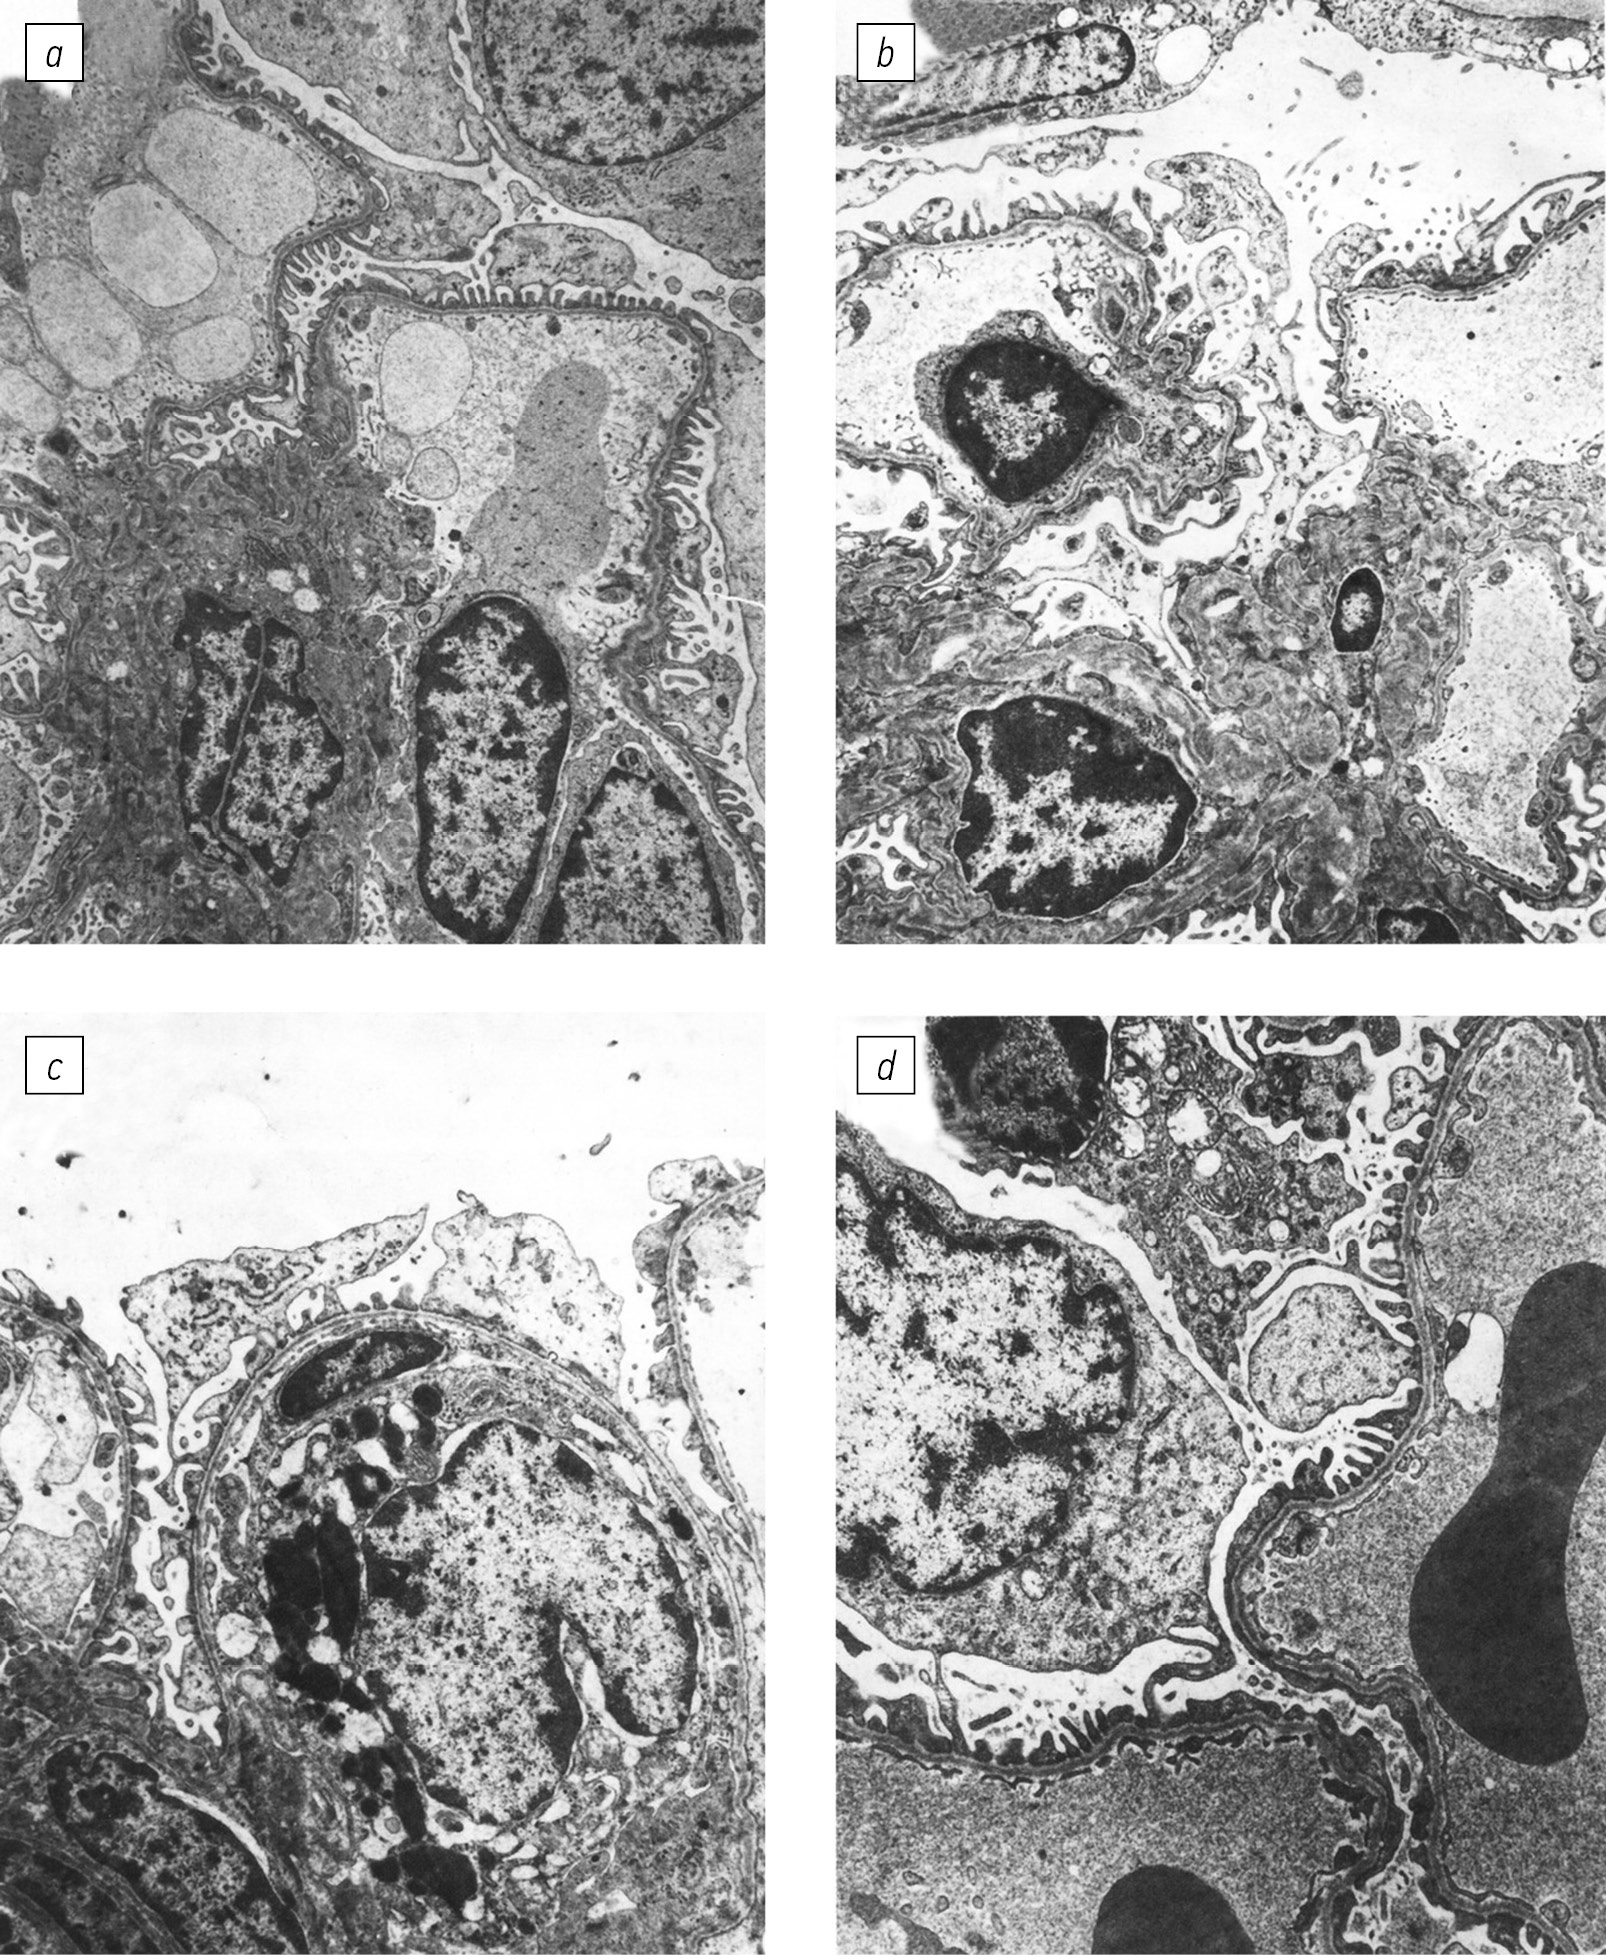

Fig. 5. Morphological changes (shown by arrows) in the myocardium of the rabbit after injection of Streptococcus pyogenes type M1, binding the Fc fragment of human or rabbit IgG [45]: a–c — the destruction of mitochondria and myofibrils (ТЕМ ×16000, 16000 and 24000, respectively); d — the morphology of the normal rabbit myocardium, which received injection of control IgG Fc-negative strain (ТЕМ ×16000)

The changes in the rabbit’s myocardium were characterized by pronounced destructive-degenerative changes in the sarcoplasm and myofibrils. In particular, there was a partial or complete disintegration of the cristae, destruction of the matrix, and a decrease in glycogen in sarcoplasm with a large number of hypertrophied mitochondria. The damage, mitochondrial destruction, and sarcoplasmic edema were observed in the marginal zones of muscle fibers near the basement membrane of capillaries, where signs of myofibril destruction also appeared (Fig. 5). A pronounced inflammatory reaction was also noted. The eviction of monocytes from the bloodstream into the perivascular space’s serous-fibrinous edema zone was observed in the capillaries of the myocardium. This was likely due to the activated monocytes/macrophages’ enhanced production of pro-inflammatory cytokines, which damaged the mitochondria, especially in the cardiac muscle. The destruction of mitochondria also led to the disintegration of myofibrils, which were located between many myofibrils and the sarcoplasmic reticulum. The immunomorphological changes in the myocardium of rabbits injected with Fc-positive GAS IgG can be considered comparable to rheumatic myocarditis in patients in terms of destructive changes. Conversely, there was no myocardial damage when introducing a strain of GAS negative for Fc-binding IgG [45, 88]. To establish the role of streptococcal IgG Fc-binding M and M-like proteins in inducing experimental myocarditis, we used isogenic mutants of the M22 type GAS, which were defective in either two or one of the fcr genes responsible for the expression of Mrp or Emm proteins. In rabbits injected with the original M22 strain or its isogenic mutants lacking one of the M proteins, we detected IgG and C3 complement deposits in the structural elements of the cardiac muscles, as well as increased production of proinflammatory cytokines IL-1β, IL-6, TNF-α, and the destructive-degenerative changes described above. However, none of the rabbits that received injections of the double mutant M22, lacking both M proteins, displayed deposits or destructive changes characteristic of myocarditis [45]. These experiments confirmed the role of streptococcal IgGFc-binding M and M-like proteins in initiating myocarditis in rabbits. The same proteins were also responsible for the development of experimental glomerulonephritis in previous experiments. Although myocarditis and glomerulonephritis are different complications of GAS infection caused by various M types, our results suggest that there is a common link in their genesis, which is realized through the ability of these proteins to induce an autoimmune response, leading to immune inflammation and tissue damage in organs.

In our experiments, we used rabbits to induce streptococcal myocarditis. We believed that the M and M-like GAS protein’s IgGFc-binding receptors do not significant differences in the binding of human or rabbit IgG [8]. After injecting the rabbits with inactivated M1 GAS bacterial cells, as in the APSGN model, we found that the IgG and C3 complement components had deposited in the sarcolemma, intermiofibrillar spaces, edematous interstitial tissue, and on the basement membrane of capillaries. We also detected positive staining of activated monocytes/macrophages for IL-6, IL-1b, and TNF-α in the same rabbits.